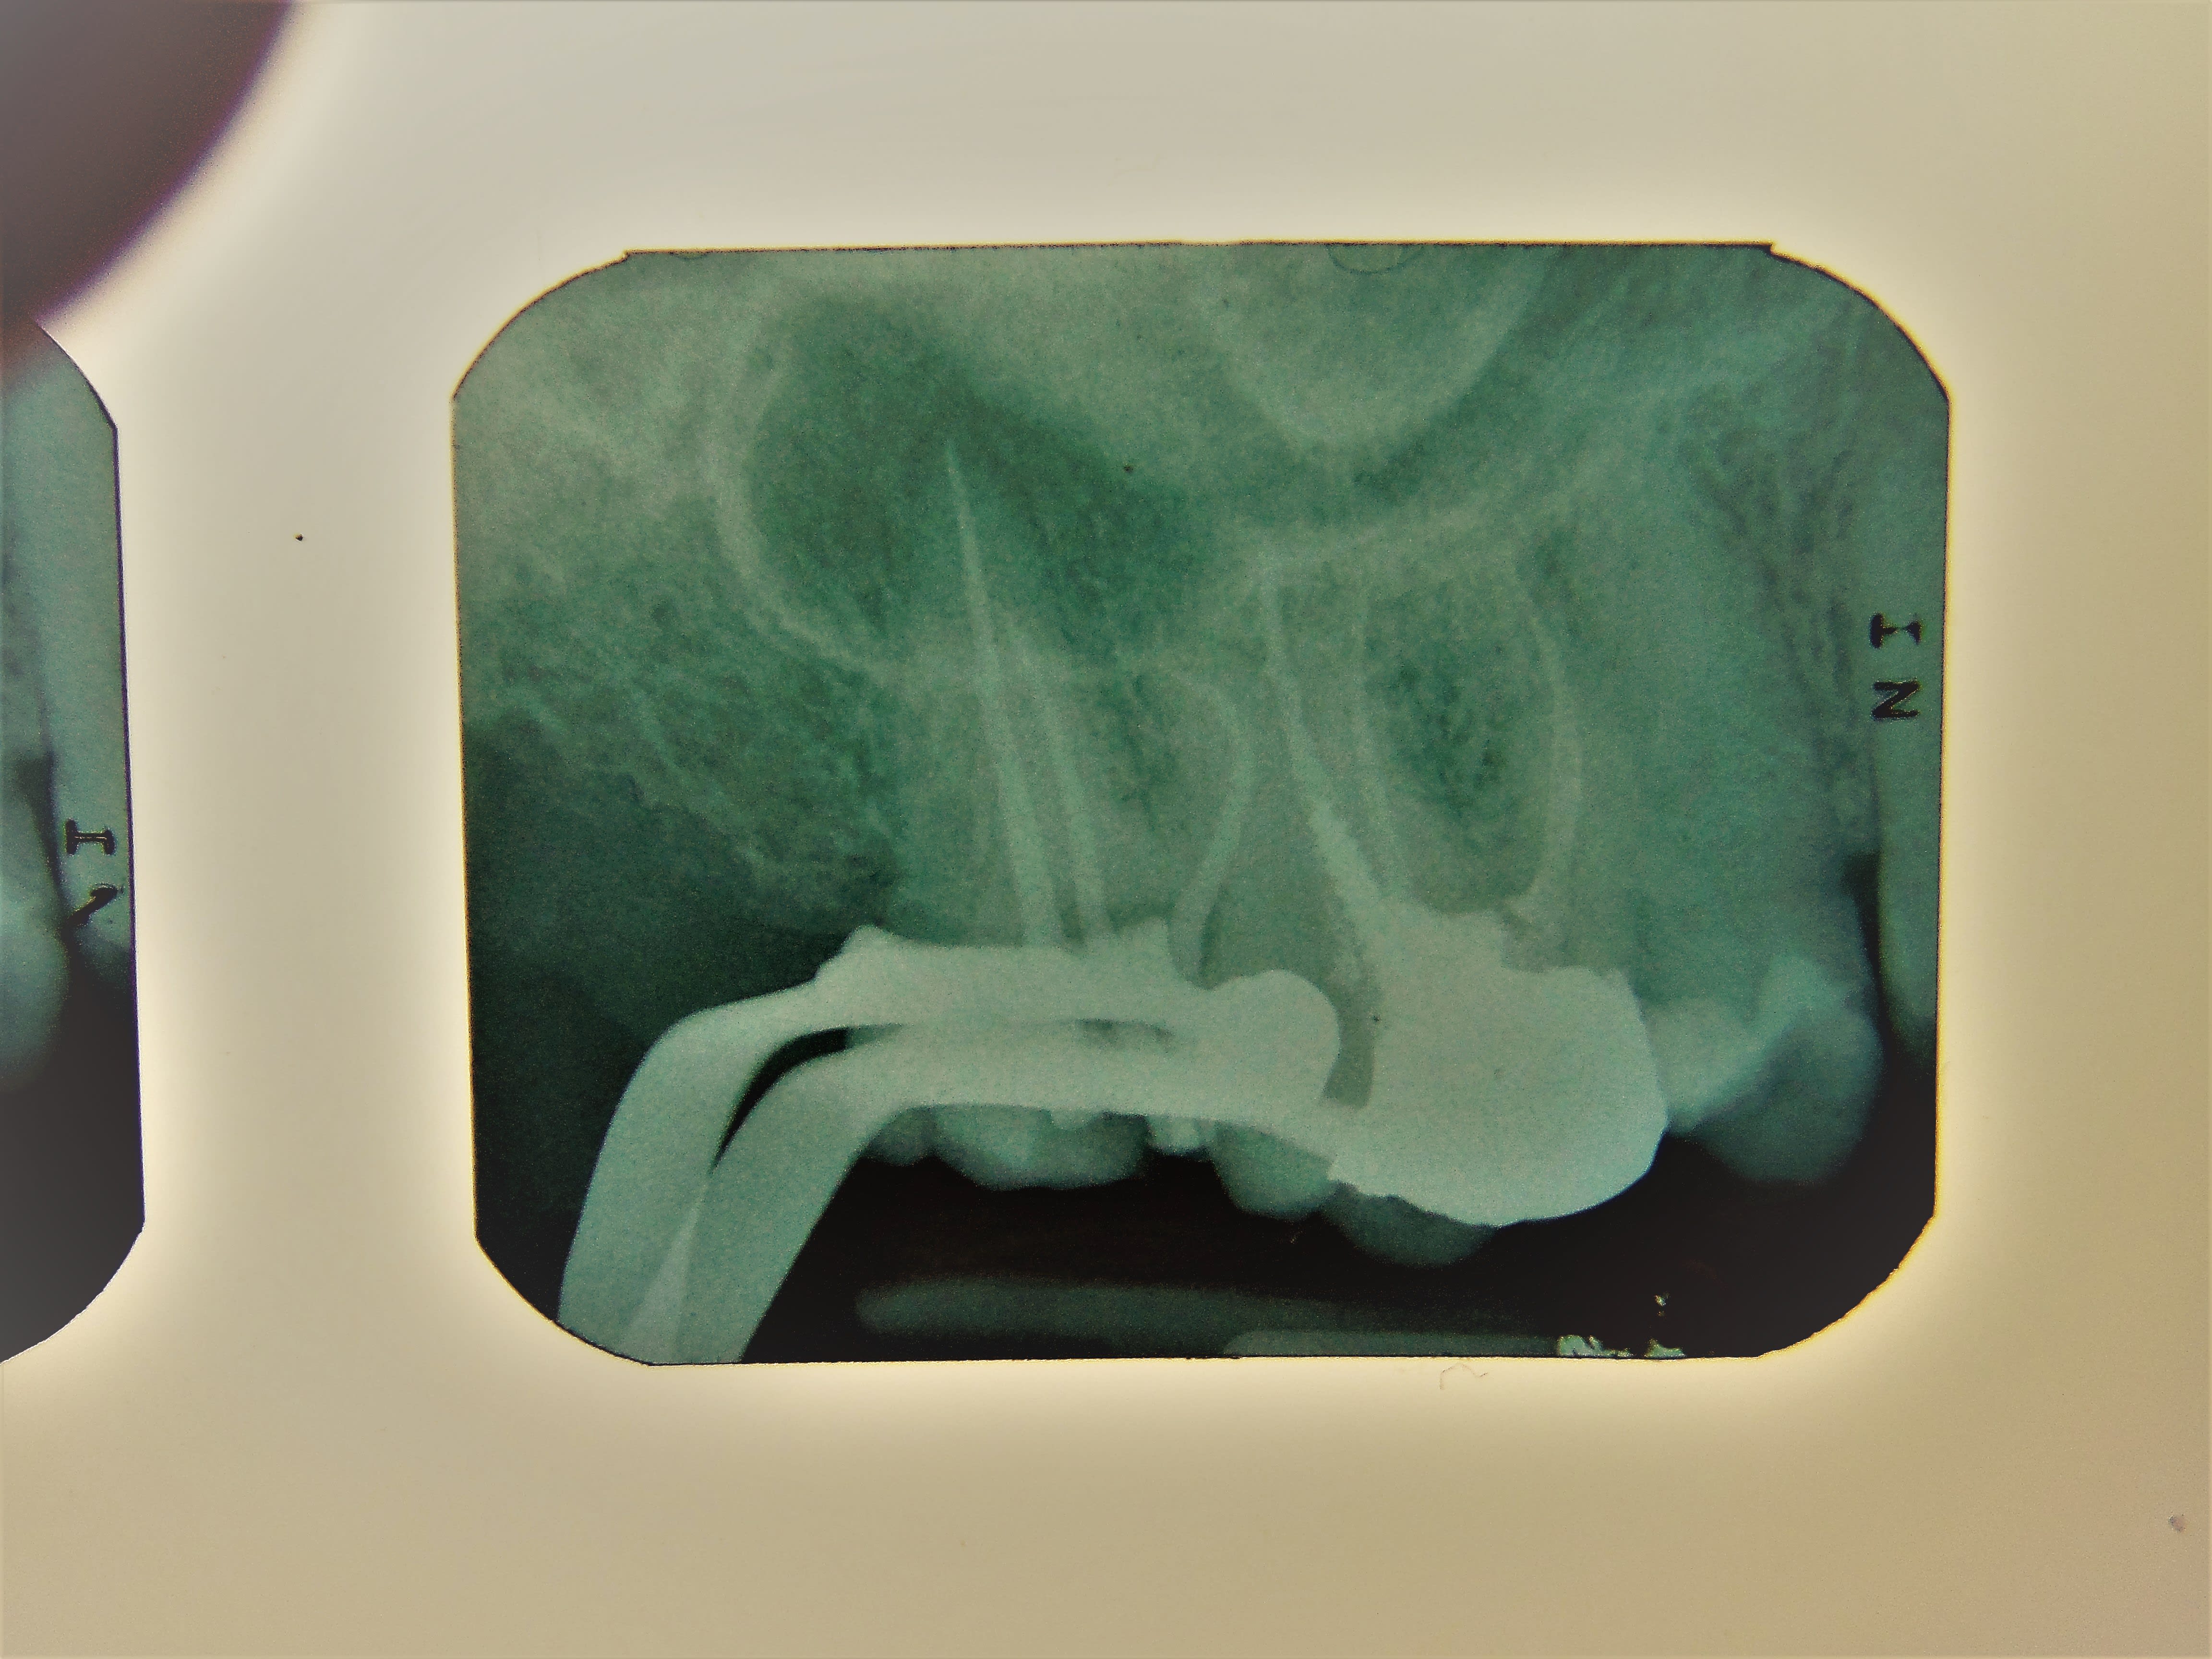

désolé , mais au petit jeu : je te le casse bien profond , j suis le plus fort .:-)

alors , ç est qui le patron ? de la caguade :-)